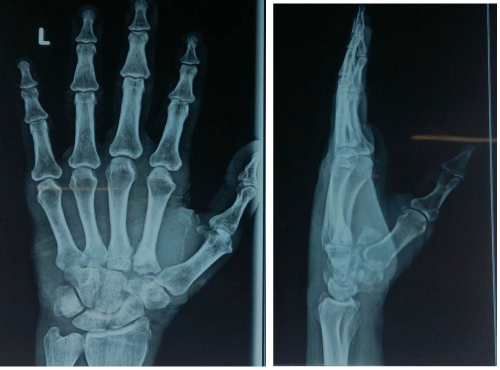

Oblique

Figure 4: X-ray left hand AP, Oblique Post-operative (60 days).